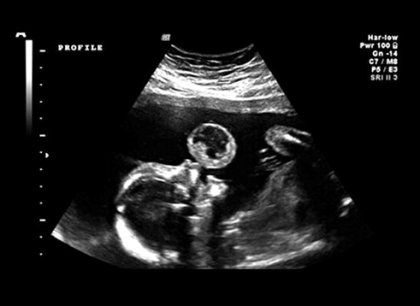

Hình siêu âm cho thấy khối u ở môi thai nhi